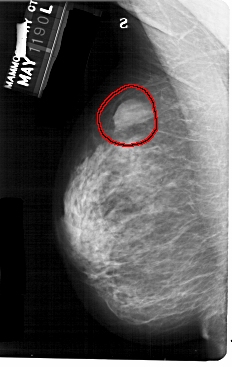

A_1303_1.LEFT_CC

LEFT_CC LINES 5491 PIXELS_PER_LINE 3211 BITS_PER_PIXEL 12 RESOLUTION 43.5 OVERLAY

FILE: A_1303_1.LEFT_CC.OVERLAY

TOTAL_ABNORMALITIES 1

ABNORMALITY 1

LESION_TYPE MASS SHAPE OVAL MARGINS ILL_DEFINED

ASSESSMENT 4

SUBTLETY 4

PATHOLOGY BENIGN

TOTAL_OUTLINES 1

BOUNDARY